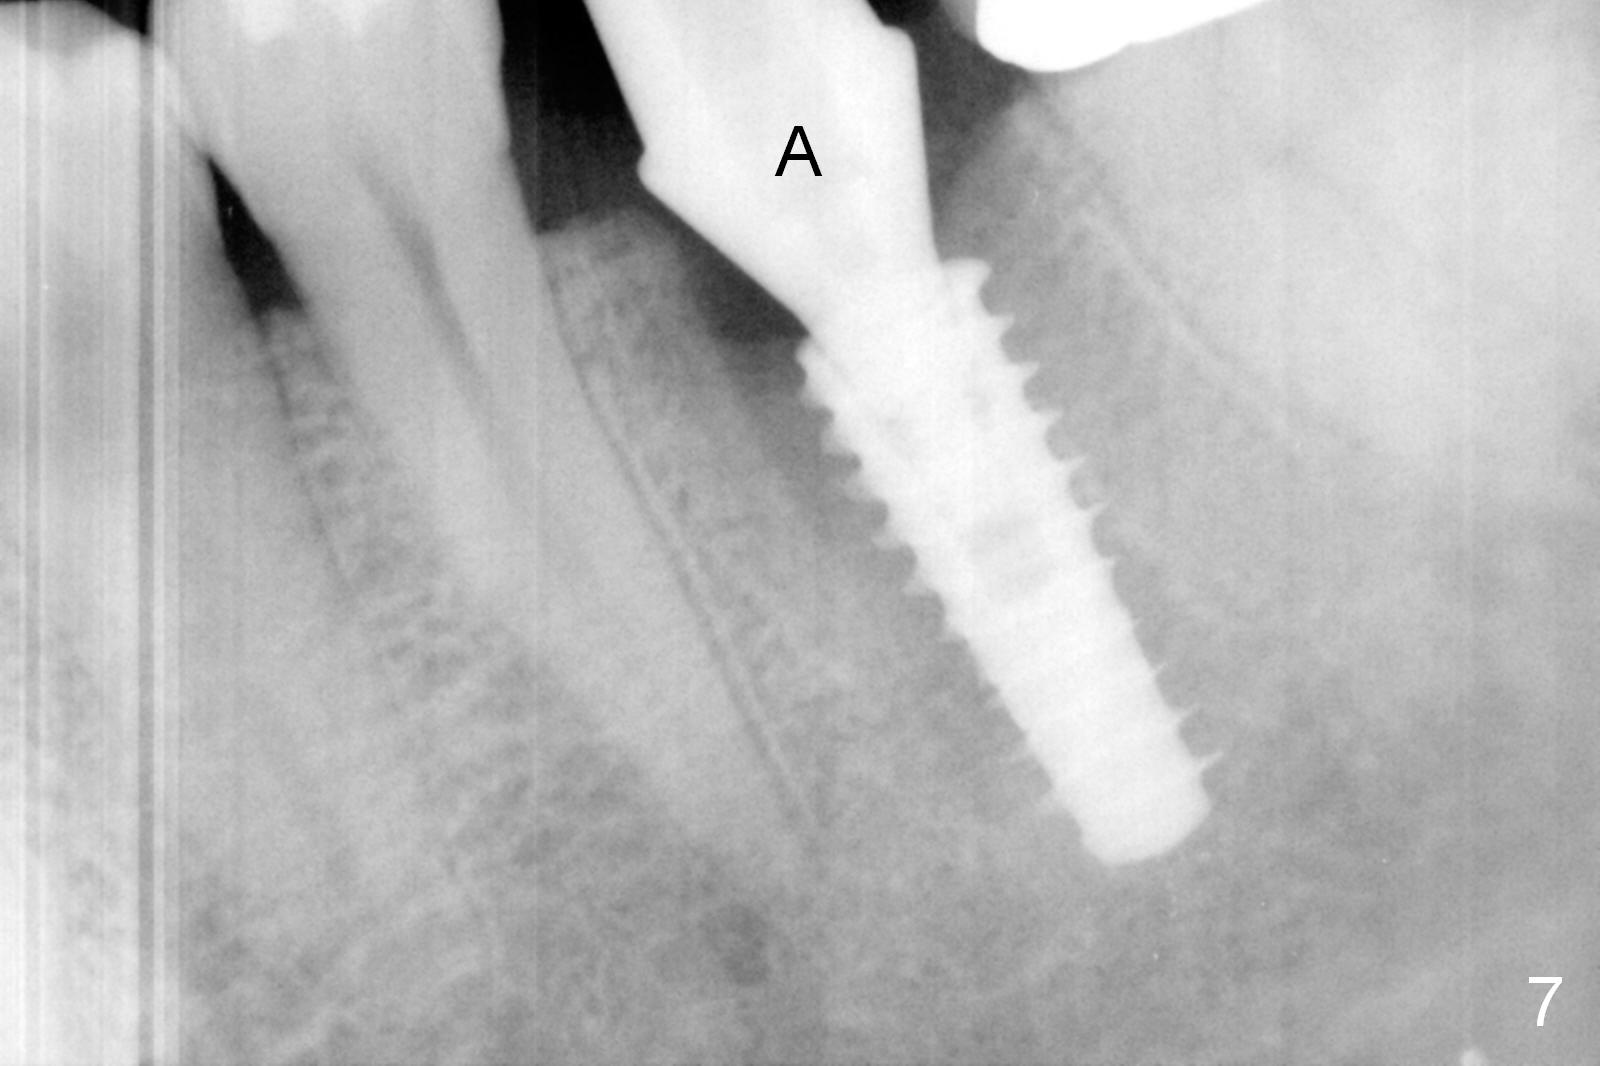

The tooth #19 is easy to get loose, but it cannot be luxated.  After sectioning and extraction (Clindamycin), the septum is found to be thin (Fig.4).  A surgical fissure bur is used to initiate osteotomy, followed by 1.6 mm pilot drill.  It is difficult to use Marking bur (wobbling over the basically pointed septum).  It is impossible to use 4.3 mm Magic Drill (MD, one drill system), since it jumps.  The smallest MD has to be used (2.8 mm).  When the next drill (3.3 mm) is being used for 13 mm with stopper (Fig.5), the patient experiences transient pain.  The depth is suggested from the design in Fig.2.  The thin septum appears not to be a reliable landmark.  When block anesthesia is administered, the initial depth should be shortened.  The drill appears to be close to the Inferior Alveolar Canal (Fig.5).  Then the depth changes to 11 mm with the following drills (3.8 and 4.3).  The mesial and distal walls of the septum are gradually perforated.  A 5x9 mm dummy implant is placed only after using 4.8 mm drill (Fig.6).  The implant appears to be short.  When a longer implant is placed (5x11 mm), it does not easily enter the osteotomy, either sliding into the mesial or distal socket with the implant separating from the implant driver.  It appears that a premount implant is appropriate in this situation.  When the 5x11 mm implant is finally seated with stability, it is 6 mm apical to the gingival margin.  The longest cuff of IBS abutment is 4 mm.  A longer implant is needed (Fig.7, 5x13 mm).  Placement is not easy as mentioned above.  Insertion torque is <20 Ncm when the patient experience a little discomfort.  A 6.5x4(4) mm pair abutment is placed (A), apparently proper for restoration.  Allograft is placed (Fig.8 *) prior to immediate provisional.  The patient complains of bad smell from the site 24 days postop.  When the provisional is removed, the abutment is found to be mobile.  When the latter is removed with local anesthesia, bone graft granules are attached to the socket above the lightly mobile implant (Fig.9).  In fact the latter appears to be stable after a few turns by finger.  A healing screw is placed; the socket is closed with collagen plug and 4-0 Chromic gut sutures (Fig.10).  It appears that a larger implant should have been used to achieve higher torque.  Two months later (3 months postop), the coronal end of the implant is partially exposed.  A 5x4 mm healing abutment is placed.  It appears that the implant is stable.  The implant appears to have osteointegrated 4 months postop (Fig.11).  Impression is taken.